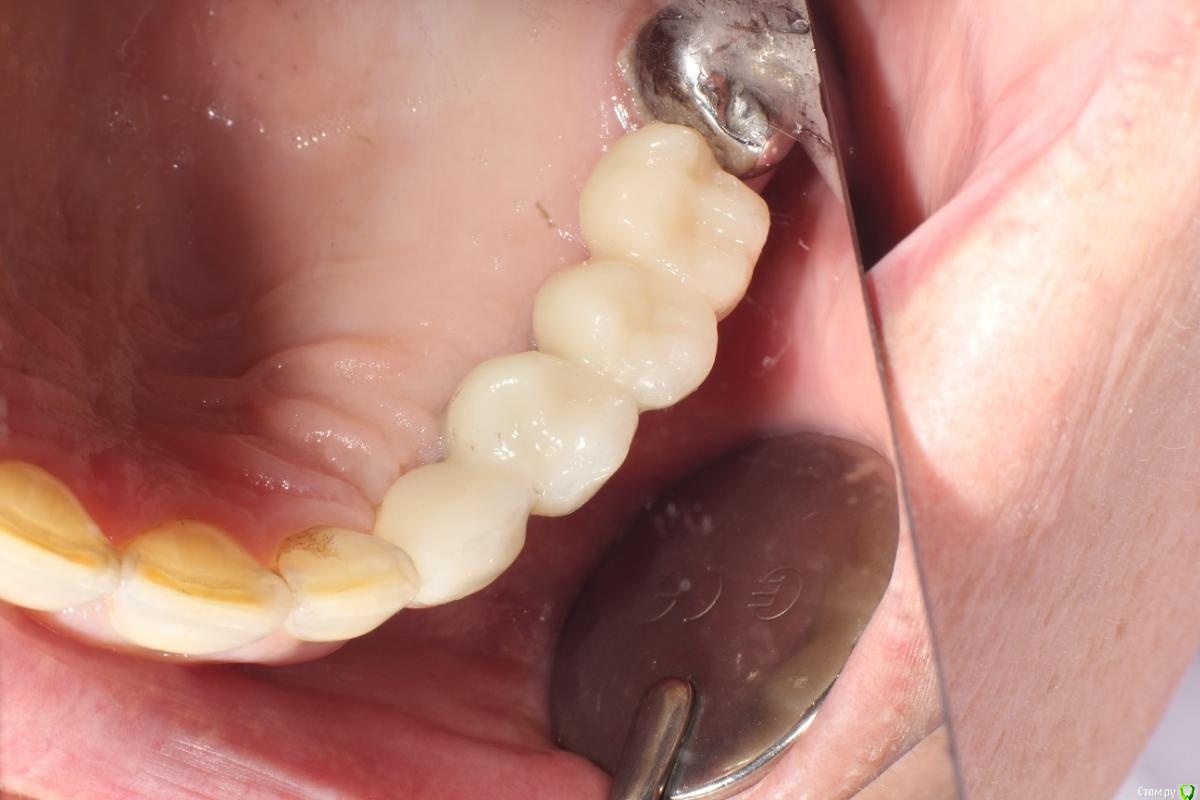

kuziy12 Опубликовано 2 ноября, 2020 Поделиться Опубликовано 2 ноября, 2020 Имплантация с синус лифтингом. Беда с позицией 2.3. Коронки на cad\cam, наносил розовую керамику и красил все сам. Сваливать не на кого) До: После имплантации: Формики: Десна: Постоянная конструкция: Улыбка: 3 Ссылка на комментарий

It'sGeorgy Опубликовано 3 ноября, 2020 Поделиться Опубликовано 3 ноября, 2020 даОбратите внимание, что там на 2.7 с гигиеной беда совсем. Думаю, что пища оттуда плавно может перекочевать под консоль. 2 Ссылка на комментарий

kuziy12 Опубликовано 9 октября, 2021 Автор Поделиться Опубликовано 9 октября, 2021 Дабы не плодить темы, выложу тут. Докрутил пациента полностью)) Ортопедия тоже моя. От переустановки импланта в области клыка отказалась. Ссылка на комментарий